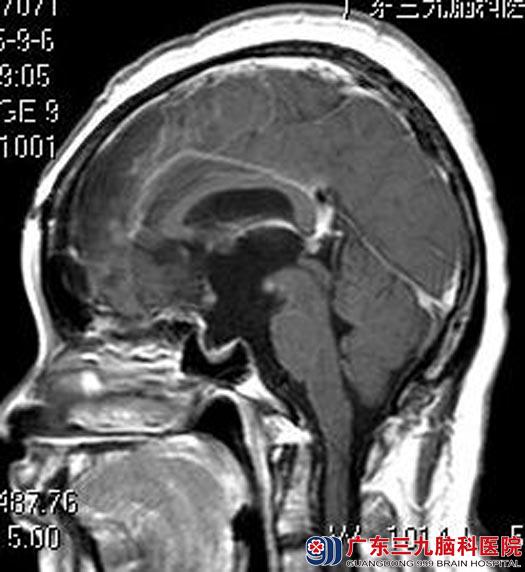

广东三九脑科医院MR检查提示:鞍区示一不规则形囊实性占位性病变,4.7cm×3.9cm×3.7cm;病变向上突入第三脑室,向后推压脑干受压变形。垂体明显受压变薄,视交叉及垂体柄受压显示不清。考虑颅咽管瘤可能性大,伴幕上梗阻性脑积水(轻度)。

由综合神经外科鲁明主任主刀,在全麻下行经额视交叉前终板联合入路鞍区巨大颅咽管瘤切除术,术中见肿瘤呈灰白色,质软,部分钙化,镜下行肿瘤切除,术中对嗅神经、视神经保护完好,手术顺利结束。术后王女士泌乳症状明显好转,无明显尿崩、离子等术后并发症。术后病理结果提示:颅咽管瘤。